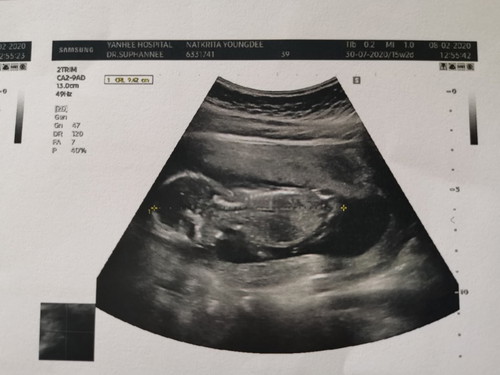

ลูกชายแม่ 15 w+4

เมื่อวานไปซาวมาค่ะ 15w หมอบอกกำลังสวัสดีคุณแม่ แม่ก็ดูไม่ออก เห็นแต่นิ้วน้อยๆ